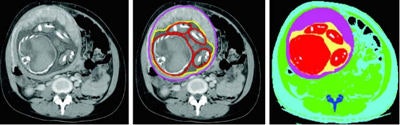

The 18 pregnant women had a gestational age between 12 and 36 weeks and underwent clinically indicated abdominal and pelvic CT exams. McMillan and colleagues created models of maternal and fetal anatomy from CT image data.

Doses were estimated using Monte Carlo simulation of tube-current-modulated scans of the abdomen and pelvis on 16- and 64-detector-row scanners (GE Healthcare). For each patient, the study team manually segmented topogram images of the uterus (modeled as soft tissue), gestational sac (modeled as water), and fetus (modeled as soft tissue or bone depending on attenuation).

The water-equivalent-diameter method measured attenuation at the image containing the 3D centroid of the fetus, McMillan said. For the Monte Carlo simulations, they used an equivalent-source method to generate scanner-specific filtration and spectrum descriptions, i.e., a simulation based on the specifications of a Somatom Sensation 64 CT scanner (Siemens Healthcare) at 120 kVp and 200 mAs with a standard bow-tie filter.